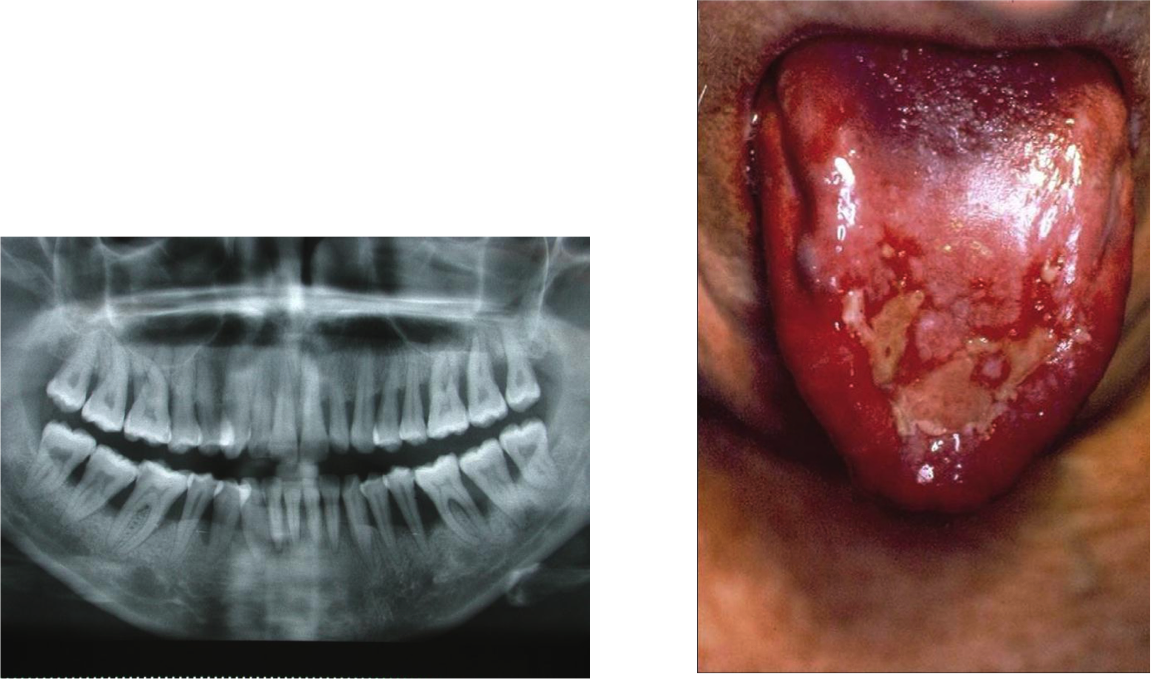

Atteinte parodontale et stomatite liée à une IRC

PUN evocatrice du VIH